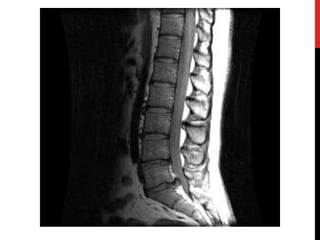

Photo courtesy NASA

An MRI scanner. See more MRI pictures and images .

In this MRI scan, you can clearly see the shattered fragments of a human wrist broken

from a fall.

Photo courtesy NASA AnMRI scanner. See more MRI pictures and images .

• 50.

Photo courtesy NASA Inthis MRI scan, you can clearly see the shattered fragments of a human wrist broken from a fall.